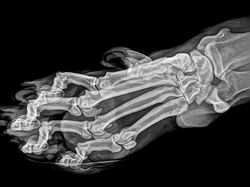

Jakarta - Kebun binatang London dan Oregon merilis foto X-Ray sejumlah hewan-hewannya. Foto tersebut kerap digunakan untuk memantau kondisi kesehatan para hewan.

Deretan Foto X-Ray Para Hewan